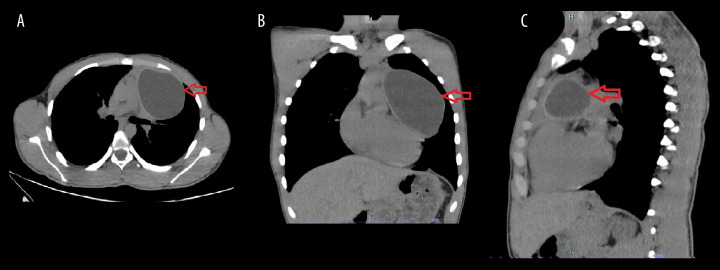

背景:包虫病仍然是一个主要的临床问题,特别是在流行包虫病的地区。这种寄生虫感染是由棘球绦虫引起的。肝和肺是受影响最严重的器官。尽管肺是最常见的胸内脏器,但肺外的胸内包虫病并不常见。然而,原发性纵隔包虫病是一种罕见的疾病,而胸腺的原发性包虫病更是极为罕见。尽管视频胸腔镜手术在胸外科领域发挥着重要作用,但其在治疗胸部包虫病中的作用尚不明确。本文报告一例17岁男性胸腔镜下胸腺包虫病原发治疗。病例报告一名17岁男性因胸闷、呼吸短促3个月前来就诊。胸片上可见明显的混浊。随后的计算机断层扫描(CT)显示在左半胸有一个大的、界限明确的囊性病变,尺寸为6.5×7×11 cm。他后来被安排进行VATS手术切除囊肿,发现囊肿与胸腺有连续性。整体胸腺切除术,以确保完全切除膀胱周围。结论:该病例的独特之处不仅在于它描述了一种罕见的包虫病部位,还在于所采用的切除技术。根据我们的文献回顾,这是最早报道的通过胸腔镜切除该部位包虫病的病例之一。此外,与开胸手术相比,VATS恢复更快,术后疼痛减轻,在类似病例中的应用有待进一步探讨。

BACKGROUND Hydatid disease remains a major clinical concern, particularly in regions where it is endemic. This parasitic infection is caused by Echinococcus species. The liver and lungs are the most affected organs. Although the lungs are the most commonly affected intrathoracic organ, extrapulmonary intrathoracic hydatid disease is uncommon. However, primary mediastinal hydatid disease is a rare entity, and a primary hydatid cyst in the thymus is extremely rare. Although video-assisted thoracoscopic surgery (VATS) plays an important role in the field of thoracic surgery, its role in treating hydatid disease in the chest is not well established. This report describes a case of 17-year-old male presenting with primary hydatid cyst of the thymus treated thoracoscopically. CASE REPORT A 17-year-old male presented to our clinic with chest tightness and shortness of breath of 3 months duration. A well-defined opacity was identified on chest radiography. Subsequent computed tomography (CT) revealed a large, well-defined cystic lesion in the left hemithorax, measuring 6.5×7×11 cm. He was later scheduled for VATS to resect the cyst, which was found to be in continuity with the thymic gland. An en bloc thymectomy was performed to ensure complete peri-cystectomy. CONCLUSIONS This case is unique not only because it describes a rare location of hydatid disease, but also due to the technique of resection that was used. Based on our literature review, this is among the earliest reported cases of a hydatid cyst in this location resected via thoracoscopy. Furthermore, compared with thoracotomy, VATS offers faster recovery and reduced postoperative pain, and its application in similar cases should be further explored.